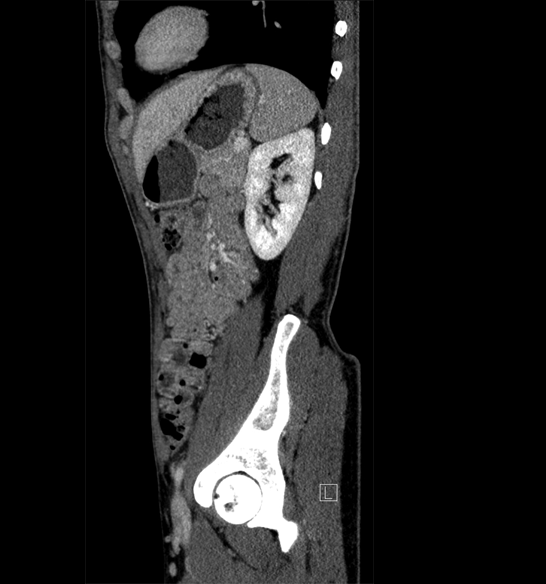

Body

Covers abdominal CT anatomy.